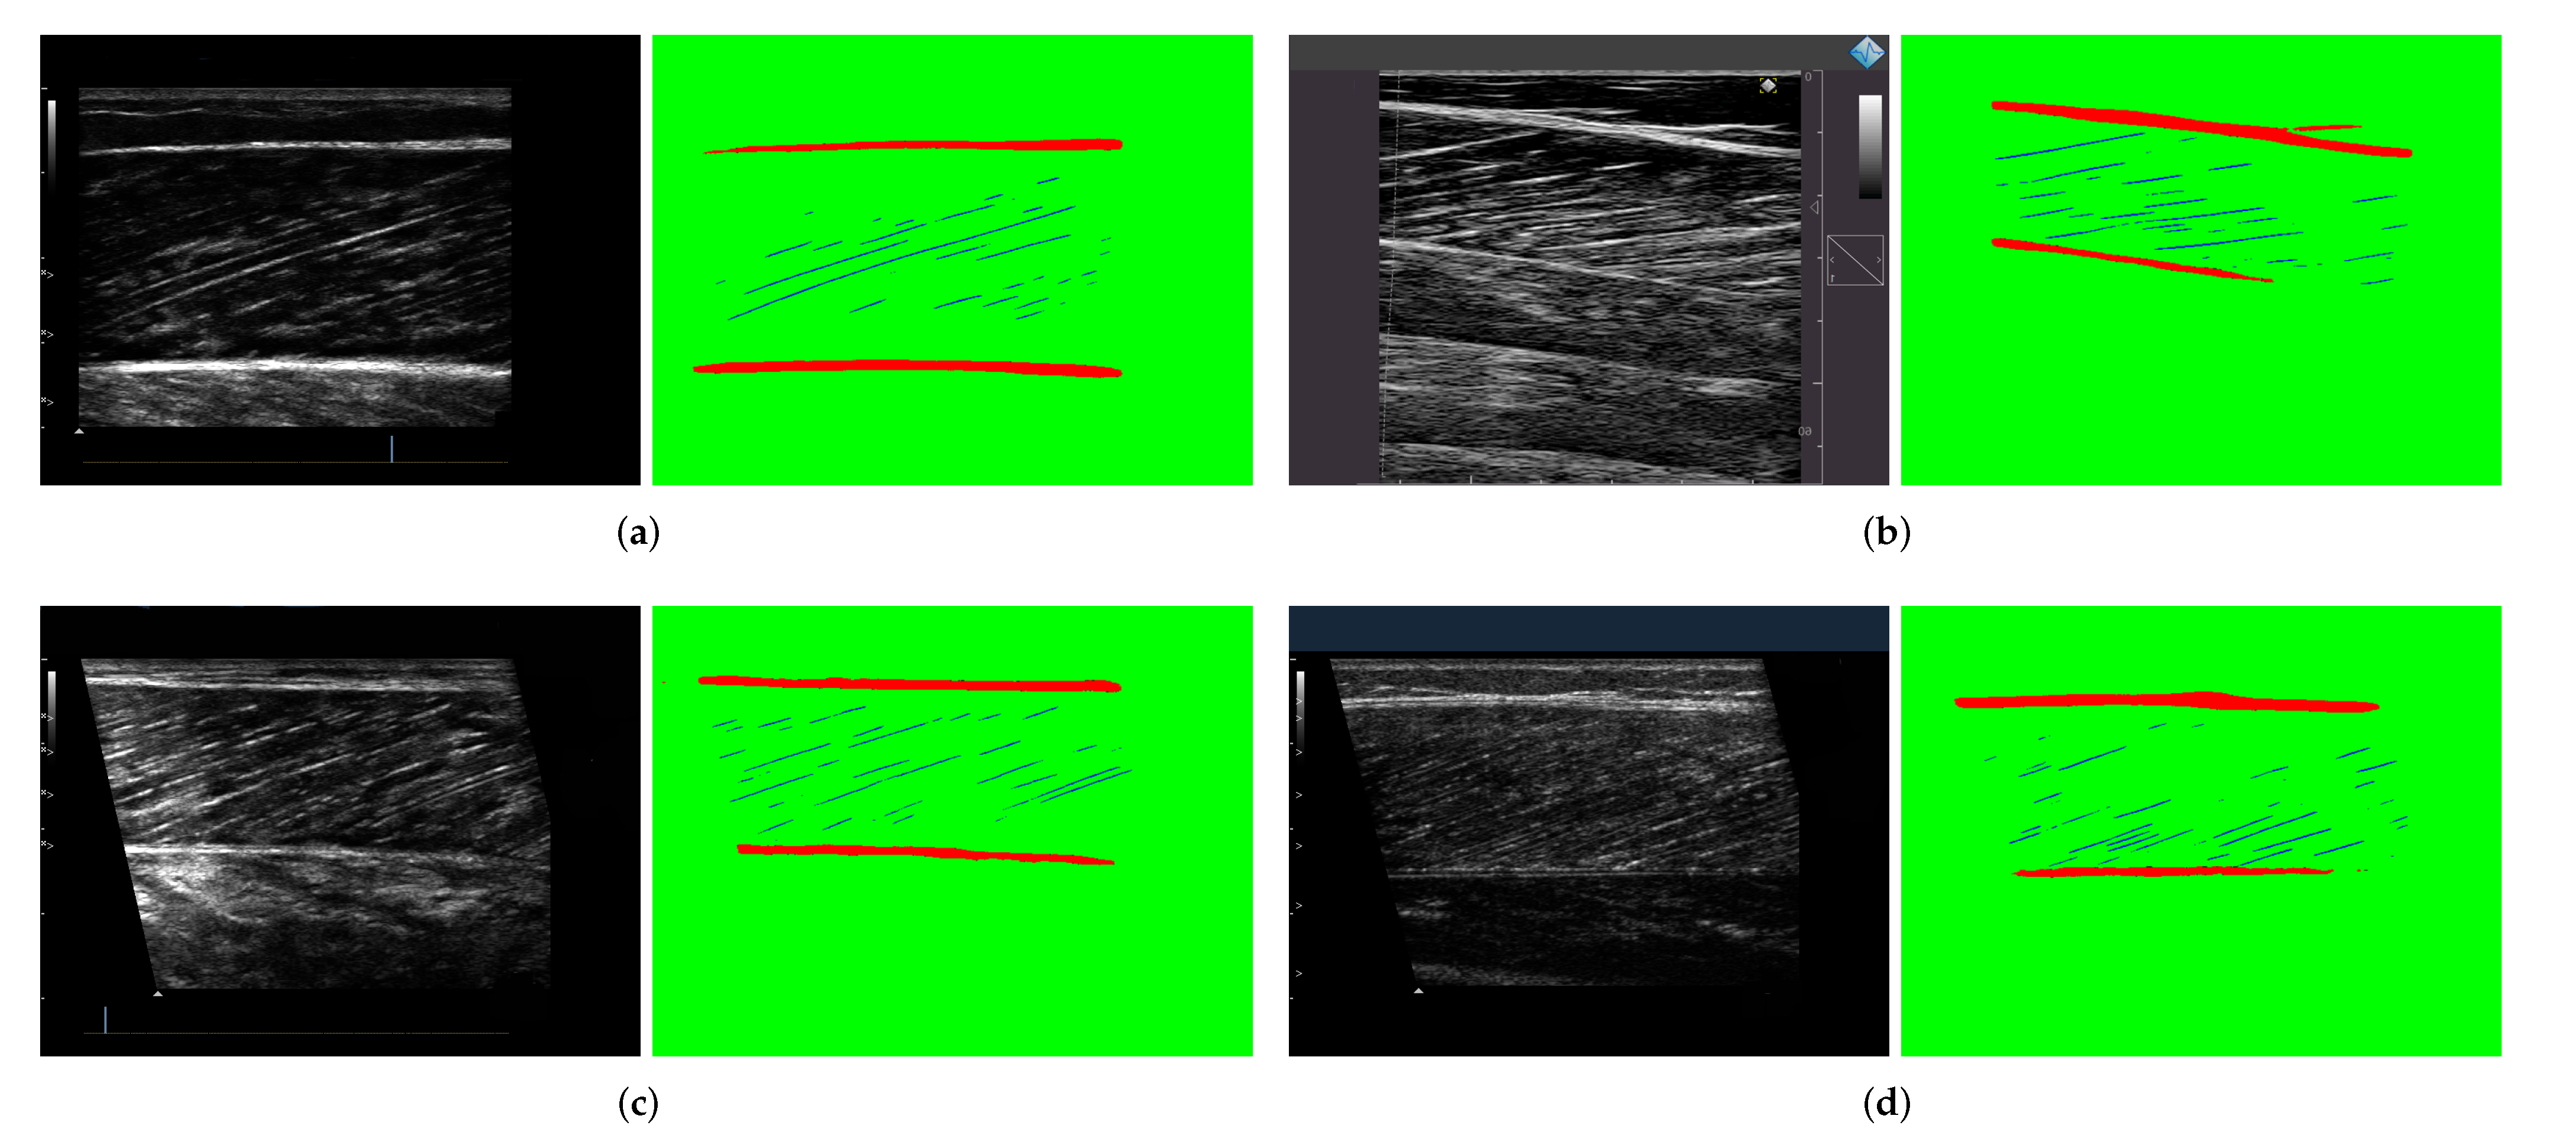

3.3. Segmentation results